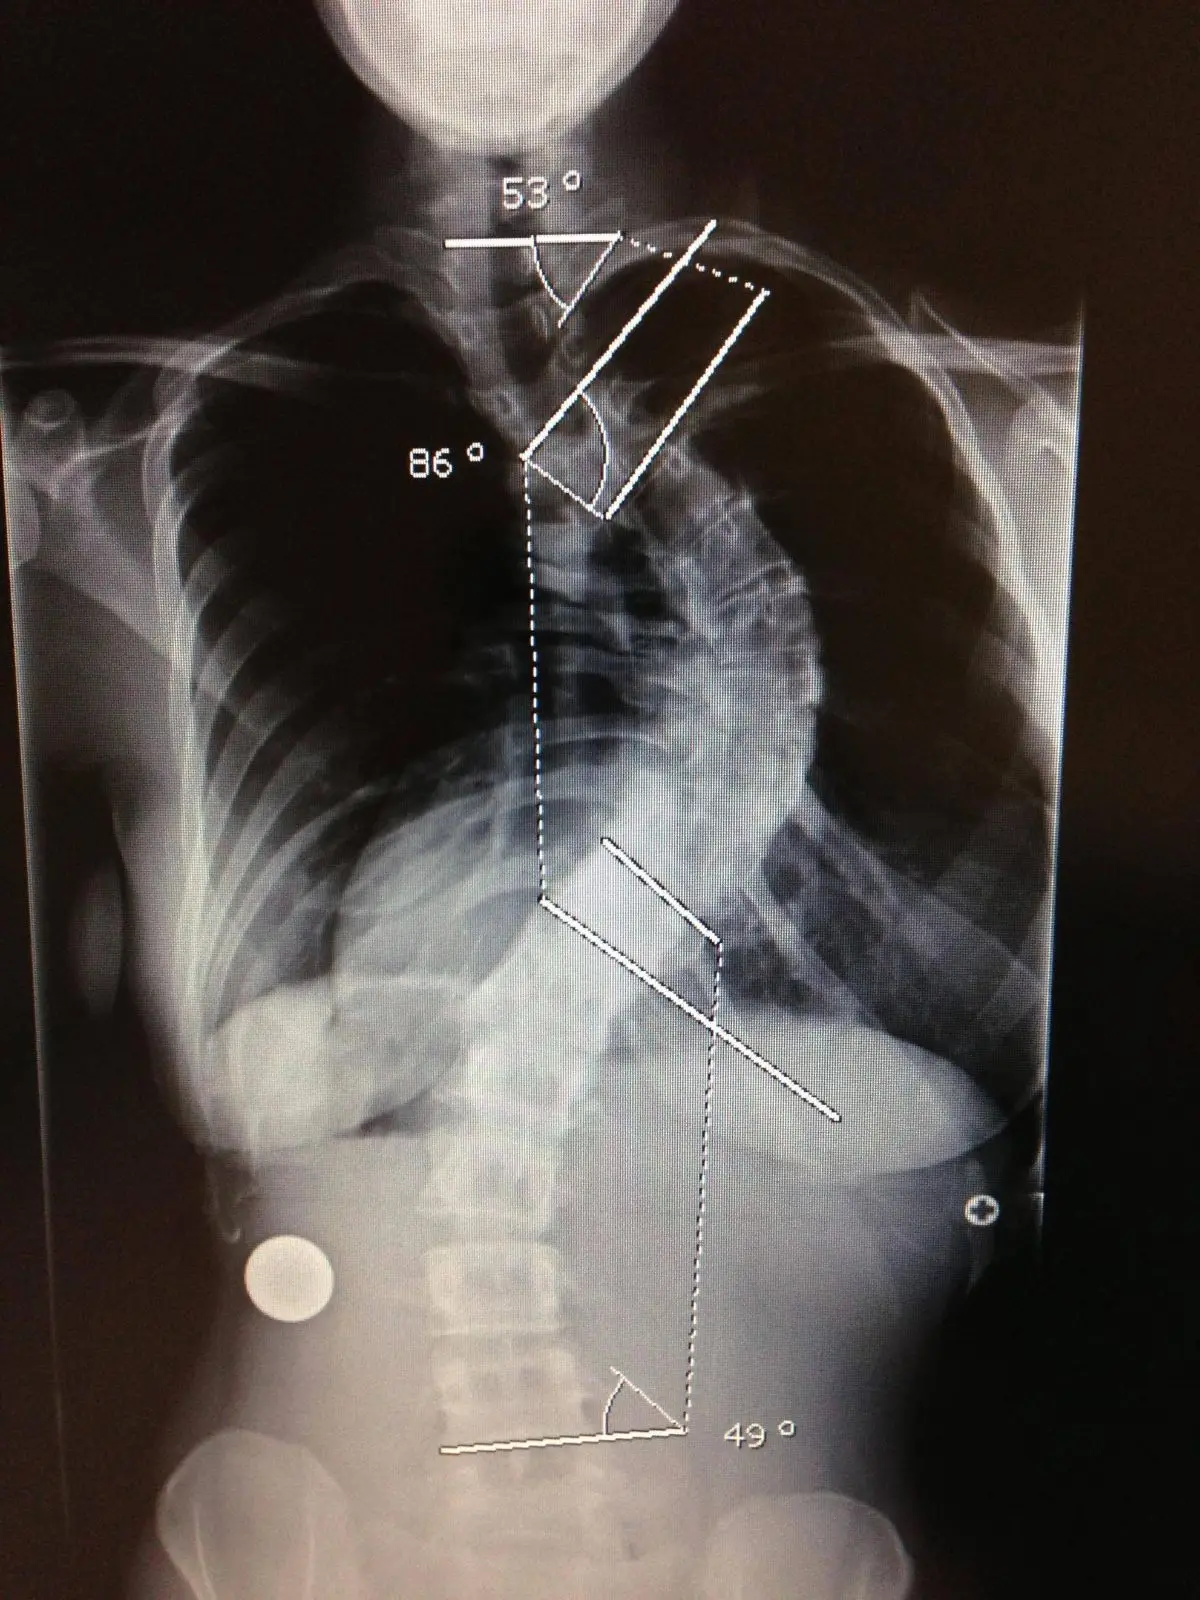

ทว่าสำหรับกรณีของหญิงสาวรายนี้อาการของโรคค่อนข้างแย่มากๆ เนื่องจากกระดูกสันหลังของเธอนั้นมีความคดของกระดูกสันหลังประมาณ 90 องศา และเธอจำเป็นต้องได้รับการผ่าตัดแก้ไขโดยแพทย์ผู้เชี่ยวชาญ และหลังจากที่แพทย์ได้ทำการผ่าตัดได้สำเร็จ ก็สามารถลดความโค้งของกระดูกสันหลังลดลงกว่า 20 องศา